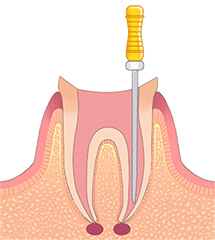

STEP01虫歯の除去

虫歯になっている部分を取り除きます。しっかりと取り除くことで、再感染を防ぐことができ、根の治療を行う環境を整えます。

虫歯の部分があまりにも大きく、健全な歯の組織が少なすぎる場合には、根を残すことができない場合もあります。 -

STEP02抜髄・感染根管処置

歯の中の歯髄を取り除きます。これを抜髄と言います。既に根の治療がされている歯が再感染を起こし、炎症がある場合や、歯髄が既に死んでしまっている状態の場合は感染根管処置と言い、中に入っている感染が疑われる物質を取り除きます。